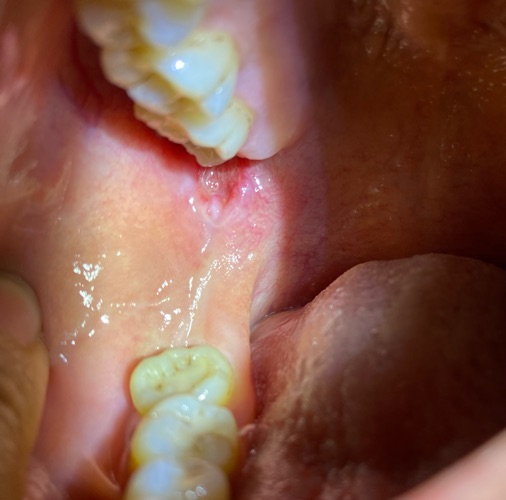

Bs cho e hỏi là e bị tình trạng này hơn 10 ngày rồi ạ. Em nghĩ là nhiệt miệng nên mua thuốc sức đẹn về sưc nhưng vẫn không khỏi. Nhờ Bs tư vấn giúp em ạ!

Xin chào bạn mình đã sức thuốc gì. Và có triệu chứng gì ko